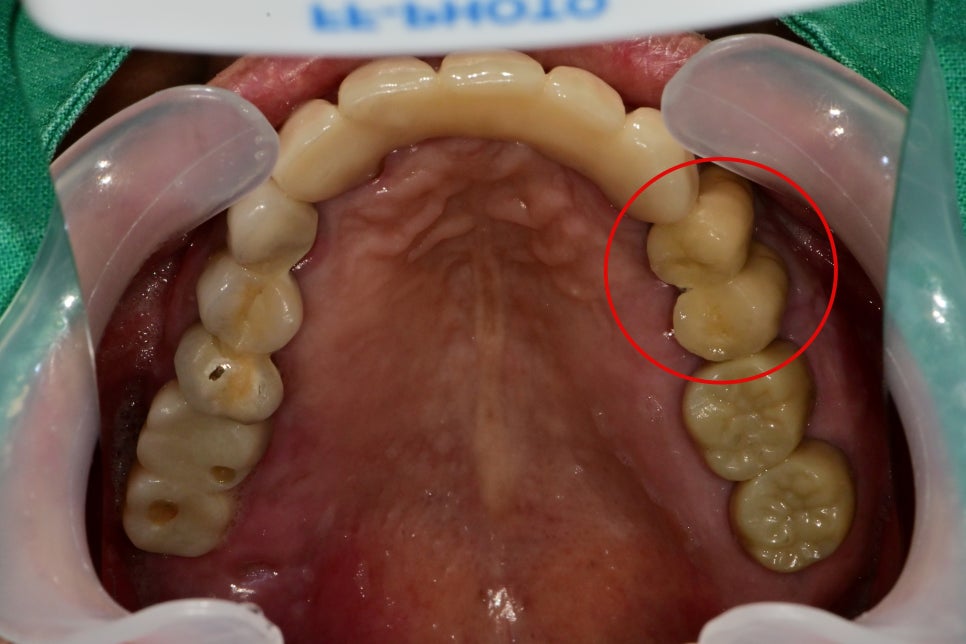

구강 내 사진에서는 겉으로는 전혀 문제는 없어 보이지만

건드리거나 씹을 때 통증을 호소하셨습니다.

구강 내 사진을 보더라도 역시 겉에서는 전혀 문제가 보이지 않습니다.

하지만 주변 잇몸을 눌러보면 피와 함께 고름이 안쪽에서 나오고

흔들거리며 통증을 호소하는 것을 확인했습니다.